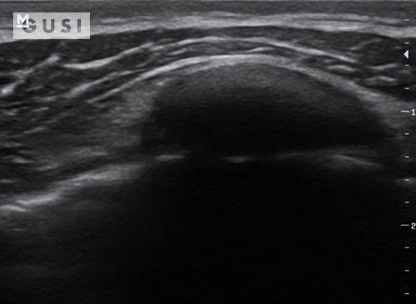

During the 2018 World Taekwondo Junior Championships in Hammamet, Tunisia, a 17-year-old male junior Taekwondo athlete took a fall, landing on his right shoulder. He exhibited a markedly limited range of motion in the affected shoulder and experienced intense pain, leading to suspicions of a dislocation.

A pre-reduction ultrasound (A) of the right shoulder showed a pronounced gap between the humeral head (indicated by a solid arrow) and the glenoid (marked by an open arrow), suggesting an anterior dislocation. Following a shoulder reduction procedure, a post-reduction ultrasound (B) verified the successful realignment of the glenohumeral joint (solid arrow pointing to the humeral head and open arrow to the glenoid).

After the procedure, the athlete displayed a considerably improved range of motion in his right shoulder and his pain levels diminished significantly.